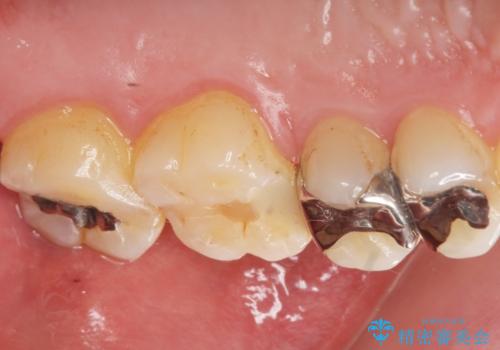

- 銀歯を白くしたい。水が少し染みるとの事で来院。

歯と歯茎の境目にプラスチック樹脂の治療の後があり、そこが染みる原因となっていました。

拡大鏡下で銀の詰め物、古いプラスチックの樹脂を外し、虫歯が残ってないかを確認して

ジルコニアクラウンで治療を行いました。